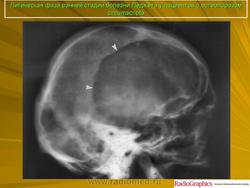

Литическая фаза.

Принято различать три фазы развития П. б.: очаговая интенсивная резорбция кости (остеолитическая, или деструктивная, фаза), смешанная фаза, когда наряду с рассасыванием кости идут процессы новообразования ее, и остеобластическая, или склеротическая, фаза с образованием типичных мозаичных структур.